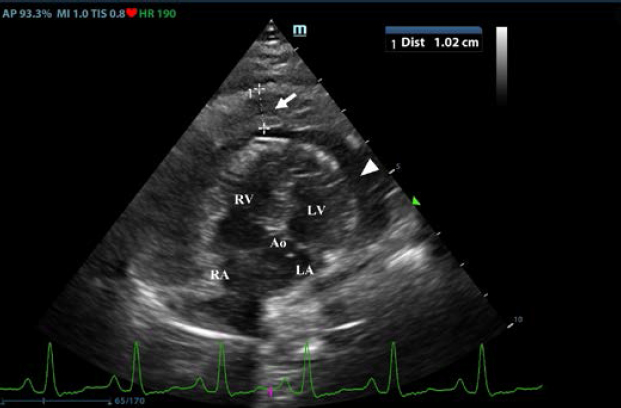

First, transthoracic echocardiogram findings were a small amount of circumferential tamponating pericardial effusion (Fig. 1) and a severe hyperechoic pericardial thickening (10.2 mm) (Fig. 2). The right atrium was normal in size and there was collapse during systole. There was mild septal flattening seen on short axis view of the left ventricle. A short-axis left ventricular M-mode showed posterior displacement of the interventricular septum during late diastole at the time of atrial systole (Fig. 3). The epicardium and pericardium had a hyperechoic appearance with a thin, shaggy layer of heterogeneous echogenic material lining the surface of each (Fig. 1, Supplementary Video I). Pericardiocentesis was not recommended at this time given that the patient was minimally clinically and hemodynamically affected. Few hours later, a second echocardiographic examination, after stabilization of left ventricular volume with intravenous (IV) lactate ringer solution at maintenance rate, showed a worsening of pericardial thickness (13 mm) and an increase in pleural effusion. Furthermore, there was a >25% mitral inflow variation noted with respiration. In addition, there was >30% tricuspid inflow variation with respiration, signs of CP. During the second echocardiography, the patient appeared to be slightly dyspneic due to the increased thoracic effusion.

Fig. 2. Transthoracic echocardiogram – left apical five-chambered view. Note the pericardial effusion (white arrowhead) and the severe pericardial thickening (white arrow). Ao: aorta; LA: left atrium; LV: left ventricle; RA: right atrium; and RV: right ventricle.